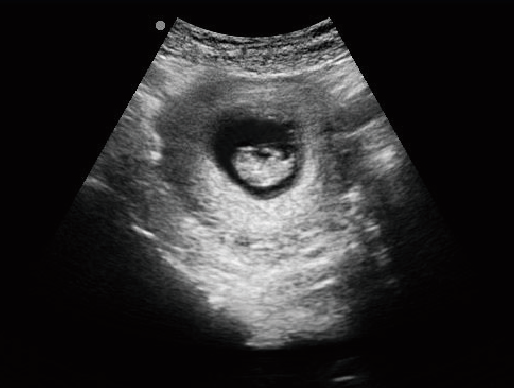

·顯示模式:B、B+B、4B、B+M、M、PW

·具有專業的動物產科軟件包,分別是狗、貓、馬、牛、羊

·適用于各種動物的臨床腹部、胸腔,心臟、肌腱、小器官、眼球、生殖系統等的檢查